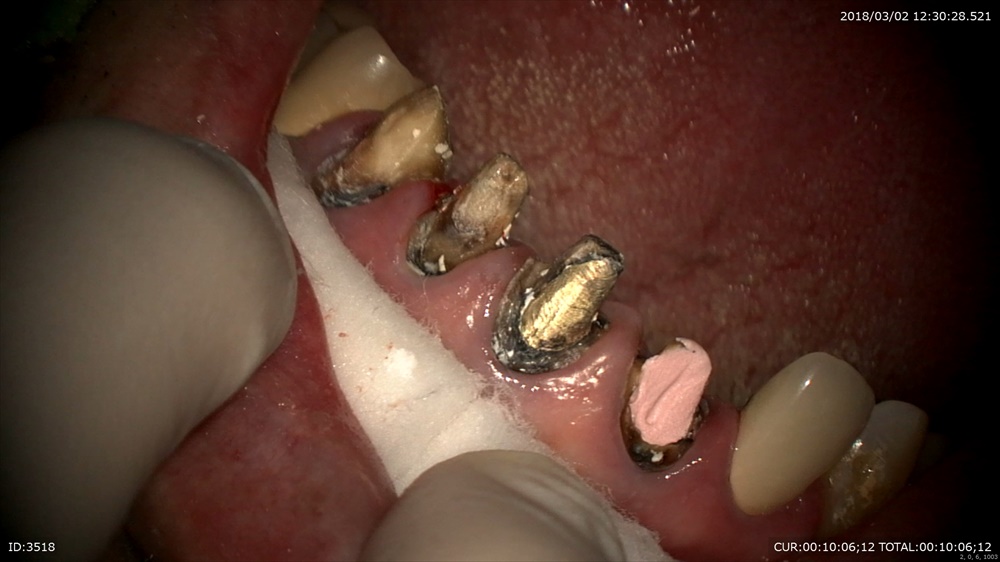

今日のケースでも

2回目の精密根管治療

ほら。温泉の様に上がってきた。